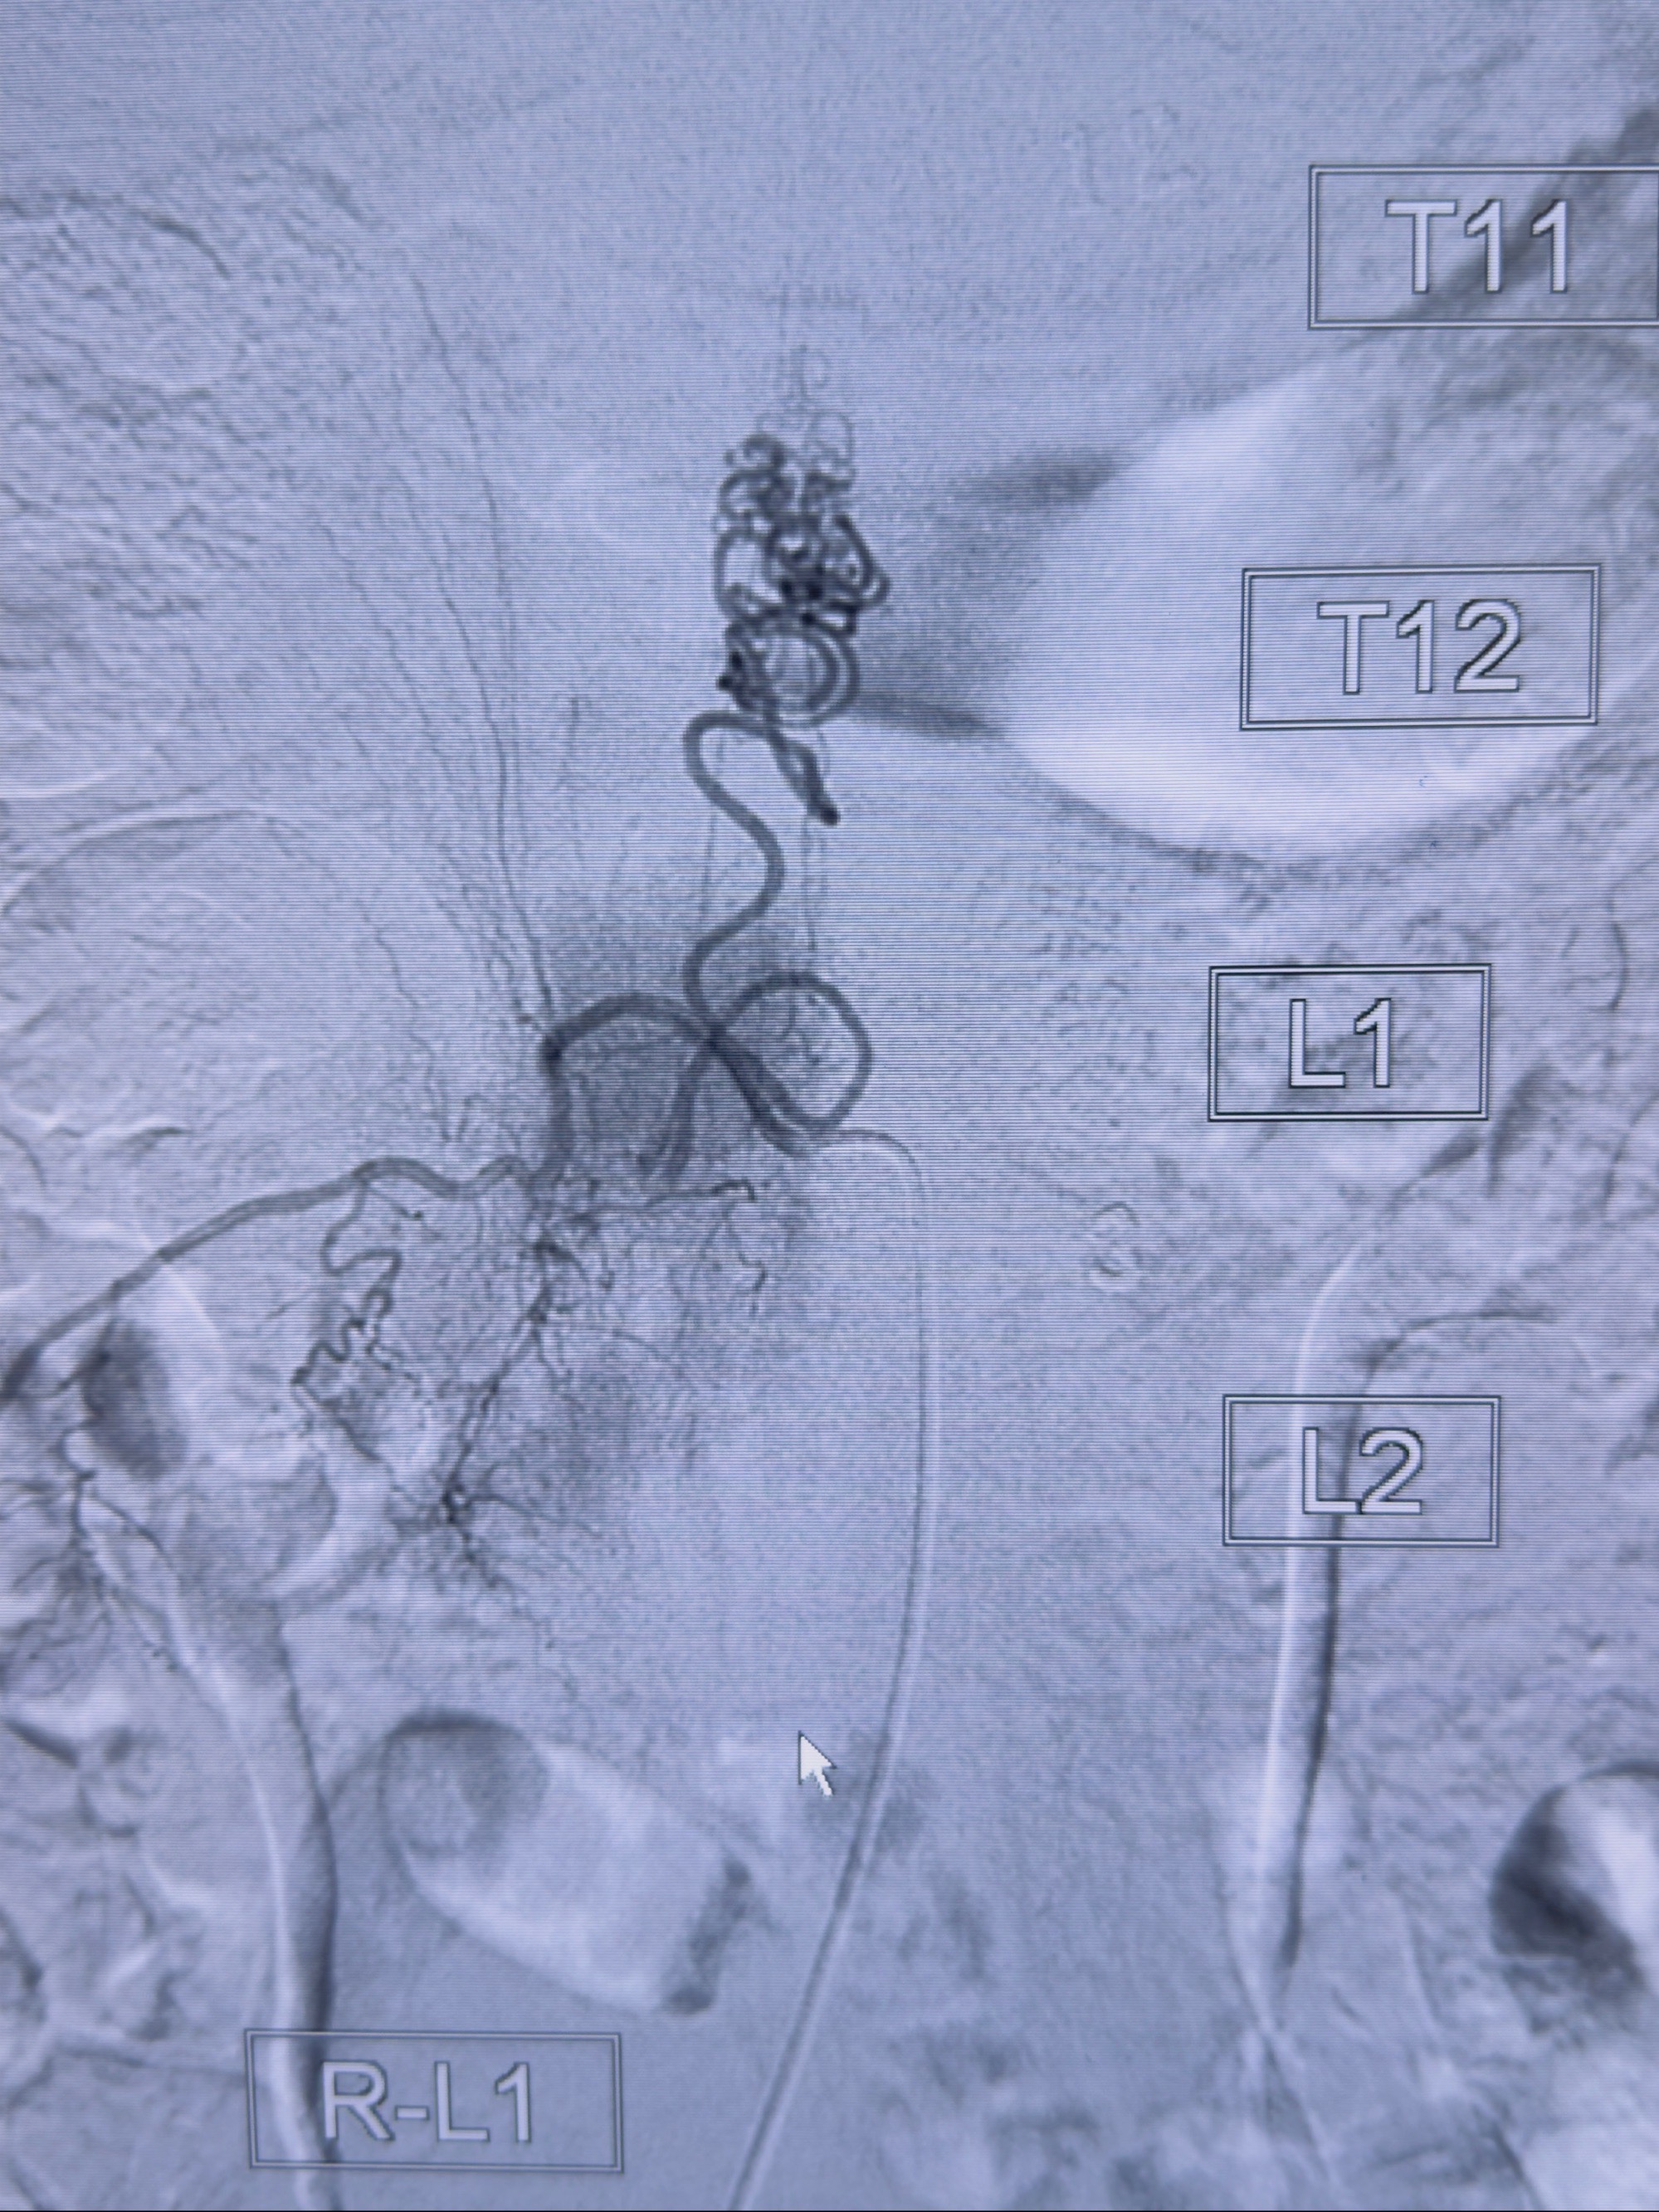

2023-10-13DSA:右侧L1水平硬脊膜动静脉瘘,供血动脉为右侧L1,附近动脉未见明确吻合供血,供血动脉处可见脊髓前动脉发出